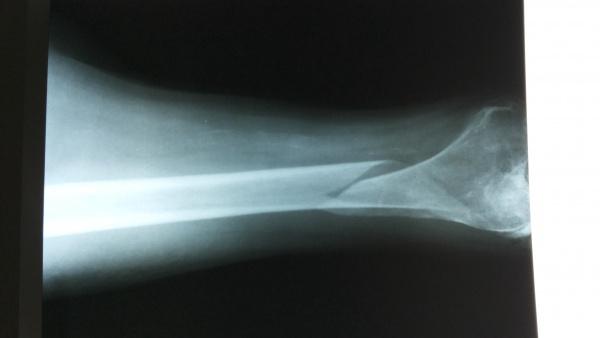

辅助检查:X片示:左股骨远端螺旋形骨折,胸片、骨盆未见外伤性改变,左膝关节退行性改变

入院时正位

牵引后床旁正位片